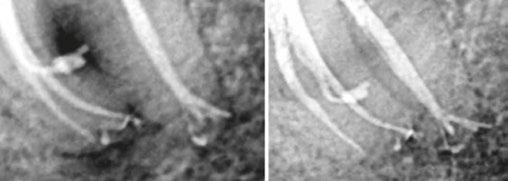

Figures 4A-4H: 4A. Preoperative periapical radiograph of tooth No. 19. Visualization of periapical radiolucency associated with mesial root is possible. Root also appears to be calcified in middle and apical thirds. 4B. Sagittal CBCT slice showing internal resorption in apical portion of mesial root. Visualization of resorptive defect perforating on distal aspect of mesial root, and significant periapical pathology extending close to furcation is possible. Defect and extent of pathology was not visualized on periapical radiograph. 4C. Axial CBCT slice showing resorptive defect encapsulating both MB and ML canals and perforating on distal aspect of mesial root. There is significant bone loss adjacent to perforating defect. 4D. Coronal CBCT slice showing internal resorptive defect encapsulating both mesiobuccal and mesiolingual canals. 4E. Immediate postop radiograph after completion of endodontic treatment. 4F,4G. Coronal and axial CBCT slice at 16-month follow-up. Note resorptive defect filled with bioceramic sealer and complete healing of adjacent bone and reestablishment of PDL. Patient returned at 16-month point for endodontic treatment of tooth No.18. 4H. Three-year follow-up radiograph. Patient remained completely asymptomatic on tooth No 19

had recently worsened. Clinical examination revealed pain to percussion on tooth No. 19. No swelling was observed, and the tooth was not sensitive to palpation or biting. Radiographic and CBCT (Veraviewepocs 3D R100; J. Morita) examination revealed a crowned tooth No.19 with perforating internal root resorption near the apical end of the mesial root, accompanied by periapical pathology extending distally to involve the distal root and coronally toward the furcation (Figures 4A-4D). A diagnosis of pulpal necrosis with symptomatic apical periodontitis was made.

The prognosis for treating the tooth with root canal therapy was discussed, along with alternative options such as extraction and replacement with an implant or bridge. Due to financial constraints, the patient opted for endodontic treatment rather than extraction. It was also explained that follow-up treatment, including an apicoectomy of the mesial root, might be necessary if the lesion persists. Informed consent was obtained.

First visit

The patient was anesthetized with 1.7 mL of 3% mepivacaine (Carbocaine, Dentsply Pharmaceutical, York, Pennsylvania) via left inferior alveolar nerve block and 1.7 mL of 4% articaine with 1:100,000 epinephrine (Septocaine; Septodont, Lancaster, Pennsylvania) via buccal infiltration. After achieving rubber dam isolation, access was made through the porcelain-fused-to-metal (PFM) crown using a combination of a round diamond bur and a No. 2 surgical length carbide round bur. Necrotic pulp was encountered. Working length was established with a Root ZX apex locator (Morita, Tokyo, Japan). The canals were instrumented to a size 35 .04 Vortex Blue rotary file (Dentsply Tulsa Dental, Johnson City, Tennessee) and irrigated with 5.25% sodium hypochlorite. The EndoActivator (Dentsply, Tulsa, Oklahoma) was used to sonically agitate the irrigant to ensure thorough disinfection of the resorptive defect. The canals were dried with paper points, and calcium hydroxide (Ultracal XS, Ultradent Products Inc, South Jordan, Utah) was syringed into the canals and defect. The tooth was then temporarily restored with Cavit (3M ESPE, Neuss, Germany).

Second visit

The patient returned after 3 weeks for completion of endodontic treatment. He reported that all symptoms had subsided. Calcium hydroxide was removed from the canals with instrumentation, irrigation, and activation with the EndoActivator. The canals were dried with paper points, and excess irrigant was removed using a surgical suction with a micro-tip. The canals were coated with BC sealer to allow for sufficient amounts of sealer to fill the resorptive defect and were then obturated with gutta percha and BC (bioceramic) sealer using the technique of warm vertical conden-

sation (Figure 4E). The occlusal access opening was restored with TPH Spectra ST composite (Dentsply Sirona, Charlotte, North Carolina), and the patient was put on a recall schedule to monitor healing. The patient returned at the 16-month point for endodontic treatment of tooth No. 18. At a 16-month recall visit, the patient was completely asymptomatic on tooth No.19. And radiographic/CBCT examination revealed complete healing of the lesion adjacent to the resorptive defect on tooth No. 19 (Figures 4F and 4G). At the 3-year recall, the patient was asymptomatic on both teeth Nos.18 and 19.